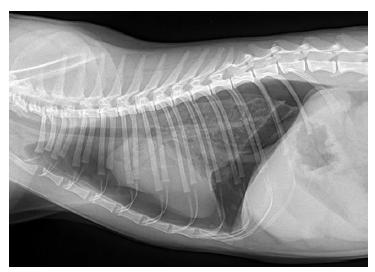

老规矩先说治疗,当喵喵因外伤(大部分气胸是由外伤导致)而表现出呼吸异常、呼吸窘迫、吸气相对费力、可能伴随鼻内出血的情况就要考虑可能是气胸,请第一时间就医!医院一般会根据X光针对病情进行判断,选择给喵喵吸氧、胸腔穿刺将气体抽出、以及开服止痛药,建议后续笼养,减少运动。

正常状态下喵喵的胸腔是封闭的,胸腔内为负压。而当空气进入的时候气压被打破了,便形成了气胸。气胸多数由于胸腔创伤或肺泡破裂引起的!气胸可分为开放性或封闭性、创伤性。在某些情况下,空气可能来自两个来源(例如,严重的胸部咬伤和肺部穿刺)大多数动物表现为呼吸急促、心动过速、呼吸窘迫和焦虑。

闭合性气胸是由胸腔内的呼吸系统产生的空气积聚而成,通常是钝性外伤如车祸)的结果,胸部受压时支气管树或肺实质可破裂,导致空气漏入胸膜腔。如果大气道受伤,可能会出现纵隔气肿。5、6根肋骨断裂可撕裂肺叶,形成闭合性创伤性气胸。

还有一种为张力气胸,张力性气胸指的是不论吸气还是呼吸胸膜腔内压总是大于大气压。也就是说只能让气体进入胸膜腔内,不能让气体出来。高于大气压的压力会使肺叶严重萎缩塌陷,比开放性气胸萎缩还要严重一些。如果单侧胸腔发生了张力性气胸,就会压迫健康的一侧,导致健康一侧的隔膜与心脏移位、变形。而对于普通气胸则会向患侧移位(患侧肺叶塌陷所致),这一点与张力性气胸相反。张力性气胸通常需要放气减压,而普通气胸需要抽气。

各类气胸喵喵都应该限制活动,肺压缩<20%时不需抽气,可给予镇咳、止痛对症治疗,有感染存在时应视情况选用相应抗生素。外伤性和医源性气胸通常采用胸腔穿刺术或插管治疗;自发性气胸通常需要手术切除受影响的肺叶。